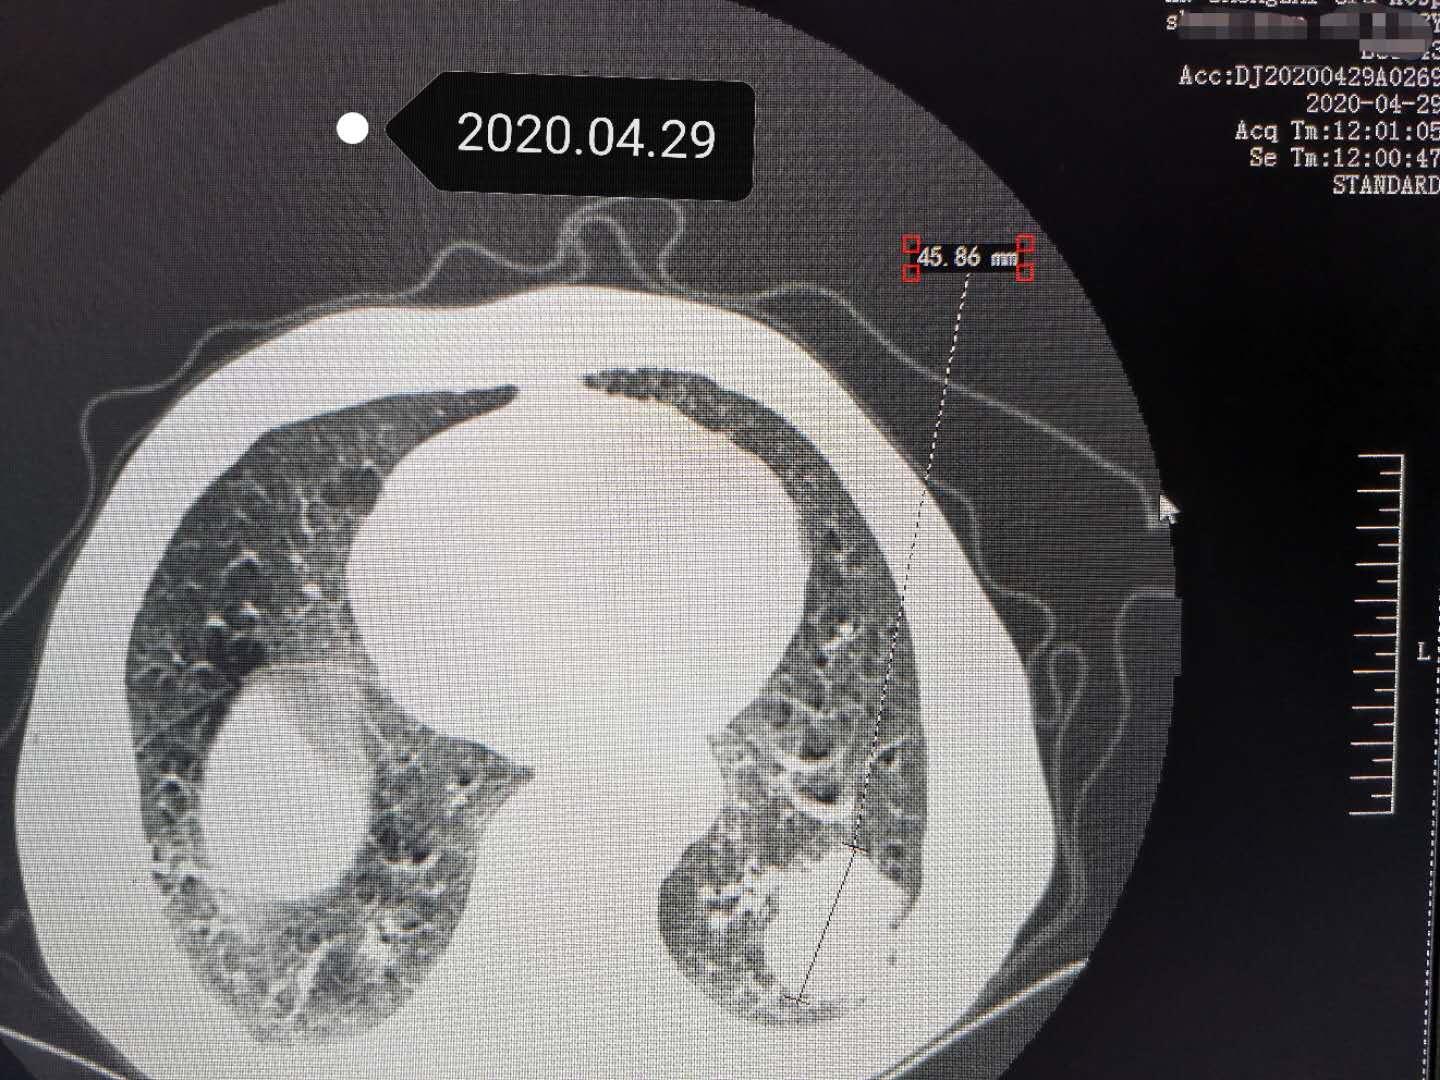

我把老爷子前几年的CT图像也调出来看看,发现去年同期的体检片子上已经有个小结节了,都没有引起太大的重视,当时诊断医师也是建议定期复查看看再说,毕竟89岁高龄了。一年时间增长了好多倍,说明肿瘤进入了“激期”,也就是进入快速生长阶段,并且向外侧侵犯了胸膜,引起了疼痛,已经影响到了老爷子的正常生活,不尽快遏制住肿瘤的快速增生,除了会造成阻塞性肺炎,转移等情况,最重要的问题老爷子的胸部疼痛会越来越重,严重降低了生活质量。

左侧肺部发现肿瘤,与胸膜粘连,引起疼痛

三个月过去了,老爷子来医院复查CT扫描,发现原来病变已经明显缩小,主要是肿瘤边界很清晰光滑了,说明已经没有活性,处于萎缩吸收阶段了。最大的收获是老爷子胸部不疼了。